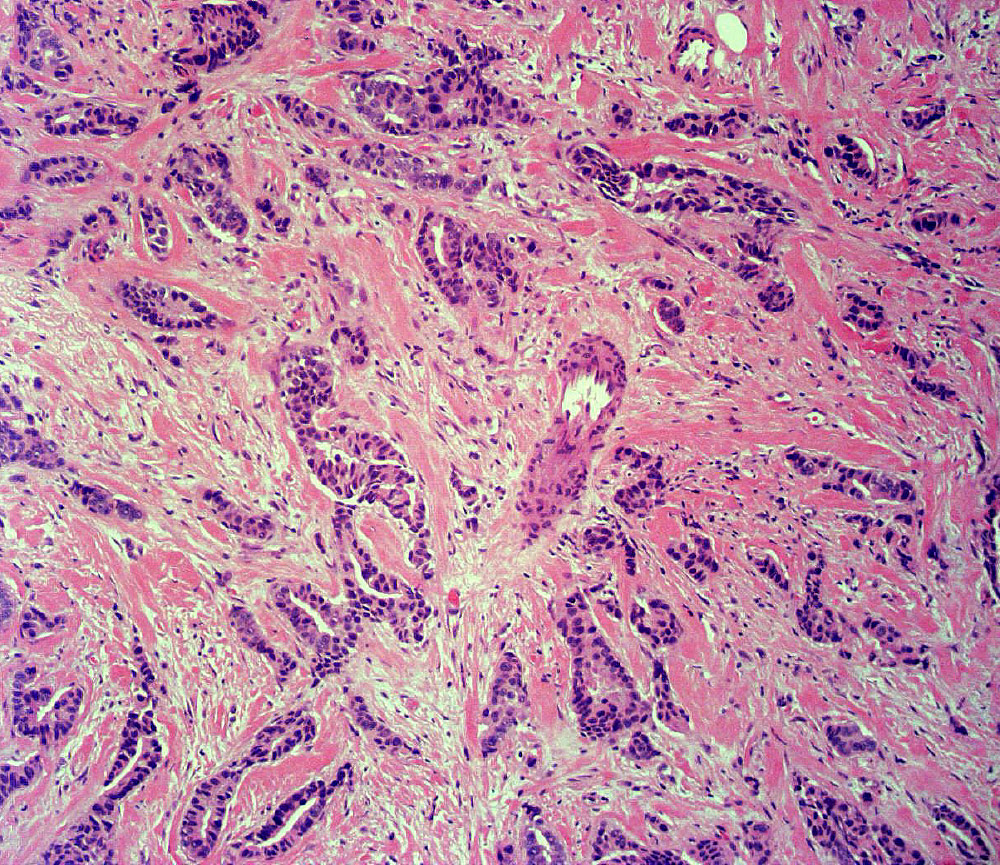

Gynecologic & Breast Pathology

Dr. Ramdall has specialized expertise in the diagnosis of various gynecological and breast disorders, including:

• Benign and malignant neoplasms